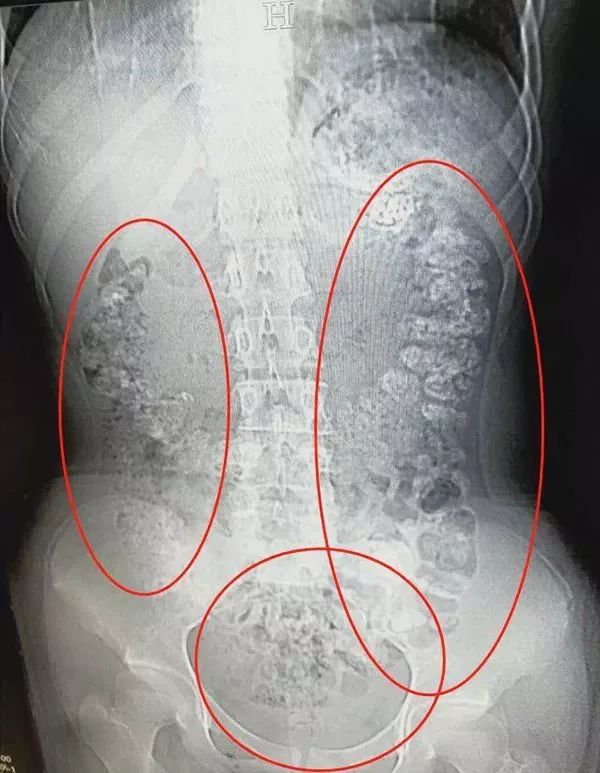

CT检查发现

胃肠道布满一颗颗圆圆的高密度阴影

——没有消化的“珍珠”。

接诊医生张楼炜见她肚子鼓鼓的,便安排了腹部CT,检查结果让他一惊:患者胃部、横结肠、升结肠、降结肠、乙状结肠,一直到肛门,全是颗粒状阴影,足有百余颗。